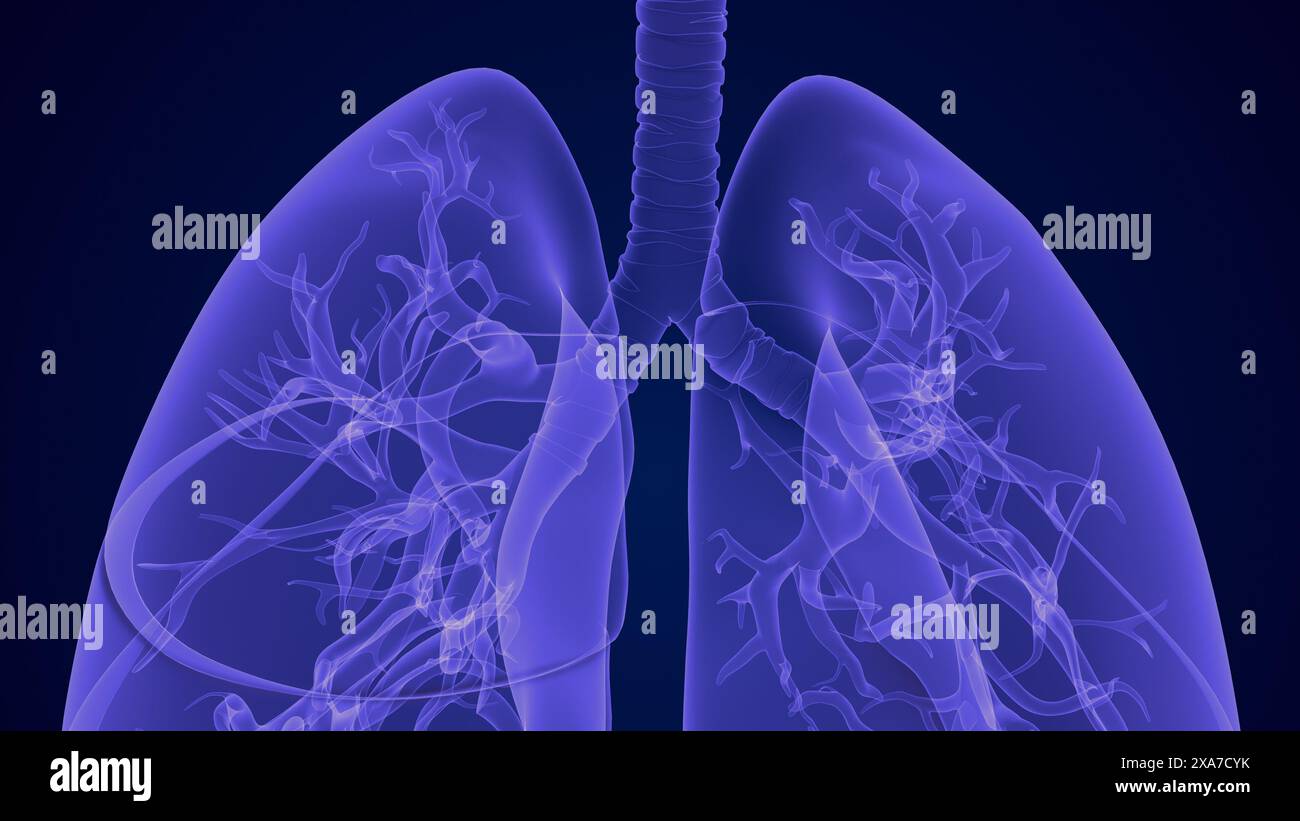

The respiratory system and the lungs Stock Photohttps://www.alamy.com/image-license-details/?v=1https://www.alamy.com/the-respiratory-system-and-the-lungs-image608596521.html

The respiratory system and the lungs Stock Photohttps://www.alamy.com/image-license-details/?v=1https://www.alamy.com/the-respiratory-system-and-the-lungs-image608596521.htmlRF2XA3Y21–The respiratory system and the lungs

3d Lungs of the Human Respiratory System Stock Photohttps://www.alamy.com/image-license-details/?v=1https://www.alamy.com/3d-lungs-of-the-human-respiratory-system-image608596299.html

3d Lungs of the Human Respiratory System Stock Photohttps://www.alamy.com/image-license-details/?v=1https://www.alamy.com/3d-lungs-of-the-human-respiratory-system-image608596299.htmlRF2XA3XP3–3d Lungs of the Human Respiratory System

The respiratory system and the lungs Stock Photohttps://www.alamy.com/image-license-details/?v=1https://www.alamy.com/the-respiratory-system-and-the-lungs-image608673287.html

The respiratory system and the lungs Stock Photohttps://www.alamy.com/image-license-details/?v=1https://www.alamy.com/the-respiratory-system-and-the-lungs-image608673287.htmlRF2XA7CYK–The respiratory system and the lungs